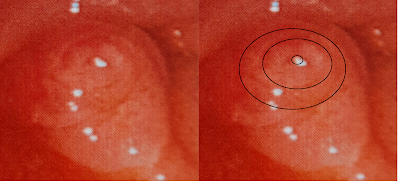

En la ecoendoscopia (Figura 2 y 3) se identificó en cabeza de páncreas lesión anecogénica (quística) de 37 mm, la cual se comunicaba claramente con el conducto pancreático principal el cual se encontraba dilatado hasta 9 mm (en su segmento más cercano a la lesión). Dentro de esta lesión quística se identificó imagen hiperecogénica (respecto a tejidos blandos adyacentes) dependiente de su pared, de 12 x 13 mm, de bordes más o menos regulares, doppler (+), todas estas características muy sugerentes de nódulo mural más que bola de mucina, sin embargo llamo la atención durante barrido ultrasonográfico que este aparente nódulo mostraba algo de sombra acústica posterior, esto nos obligaba a utilizar algún método adicional para confirmar que se trataba de un verdadero nódulo mural.

Figura 3. Ecoendoscopia: Nódulo mural y comunicación con conducto pancreático principal dilatado (9 mm)

En la USE desde el punto de vista

morfológico se encontraron varios hallazgos que llamaron la atención, el

primero de ellos la presencia de una imagen compatible con nódulo mural.

La identificación de un nódulo mural

tiene una precisión diagnóstica de hasta el 83% para detectar quistes mucinosos

con alto riesgo de malignidad [6]. Sin embargo, es conocido que la mayoría de

lesiones ecogénicas dentro de quistes mucinosos son bolas de mucina, lo cual

puede limitar la precisión diagnóstica de este estudio.

Por ello, existen múltiples reportes en donde se describen las diferencias ultrasonográficas entre un nódulo mural y una bola de mucina [7]:

- Nódulo mural: isoecogénico o hiperecogénico en comparación a tejidos

blandos adyacentes, no tienen bordes lisos y no tiene un halo hiperecogénico

periférico.

- Bola de

mucina: hipoecogénica en comparación con el tejido blando adyacente, de bordes

lisos, tiene un halo hiperecogénico periférico.

A pesar de ello, esta reportado [7] que considerando estas características la precisión diagnóstica no supera el 79 %, con moderada concordancia interobservador (coeficiente Kappa 0.44).